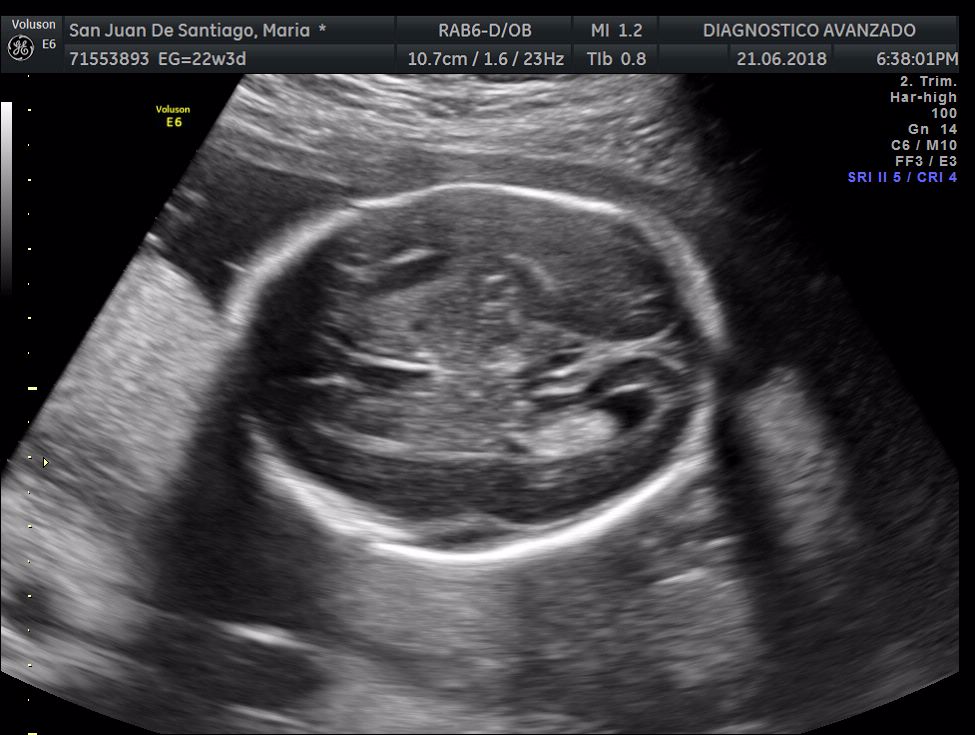

¡Hola a todos! Hoy hemos ido a hacer la tradicional ecografía 3D de la niña, os dejamos todo el material (aunque es un poco demasiado).